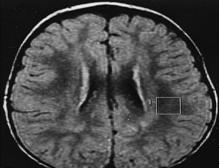

리 증후군은 여러 가지 임상 증상을 종합한 결과와 혈액 및 뇌척수액의 유산 증가, CT나 MRI 검사, 근육 생검, Respiratory chain enzyme studies, 분자 유전학 검사(사립체 유전자 검사)로 진단합니다. 1996년에 라만(Rahman) 등이 규정한 리 증후군의 진단 기준은 다음과 같습니다.

- CT나 MRI 검사에서 리 병(Leigh disease)의 특성이 나타나는 경우

질환의 진행 과정을 잘 살피고 관리하기 위해 정기적인 검진이 필요합니다. 일반적으로 신경학적 평가, MRI, EEG 검사(발작이 의심될 경우), Metabolic 평가, 유산과 피부르산염의 혈액, 뇌척수액의 농도, urine organic acids, 안과적 평가, 심장 기능 평가 등을 실시합니다. 현재 리 증후군의 근본적인 치료 방법은 없으며, 증상에 대한 치료를 시행합니다.